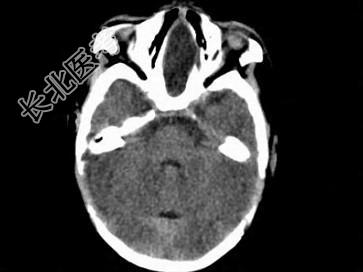

- 单项选择题两个月女婴,口咽部有一肿块, 行CT检查如图,请选择最可能的诊断 ( )

A、脑积水

B、胼胝体发育不全

C、透明隔囊肿

D、前脑无裂畸形

E、Dandy-Walker综合征